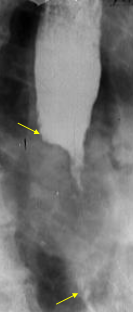

Stenoză esofagiană benignă (postcaustică)